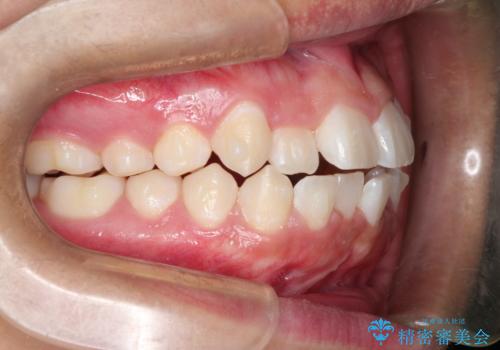

前歯のガタガタを目立たずきれいにしたい インビザラインによる見えない矯正

- 前歯のがたつきを主訴に来院されました。

上顎の前から2番目の歯の噛み合わせが反対になっていました。

抜歯矯正も考えられるケースでしたが、非抜歯での矯正を希望され、インビザラインにて治療することとなりました。

目立たずに矯正を終えることができ、患者様にも満足していただきました。